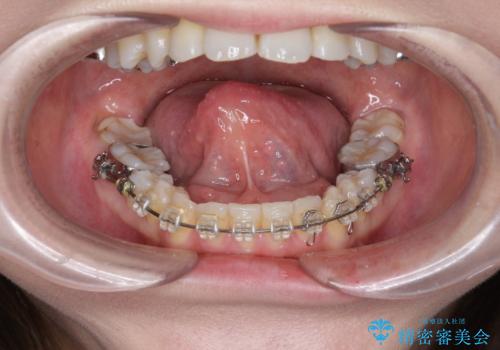

[ 舌の小帯の形成術 ] 滑舌を改善したい

担当医 大元洋佑

![[ 舌の小帯の形成術 ] 滑舌を改善したいの症例 治療前](https://seimitsushinbi.jp/wp/wp-content/uploads/2023/10/IMG_7222-500x350.jpg?v=1697768320)

![[ 舌の小帯の形成術 ] 滑舌を改善したいの症例 治療後](https://seimitsushinbi.jp/wp/wp-content/uploads/2023/10/IMG_7670-500x350.jpg?v=1697768329)